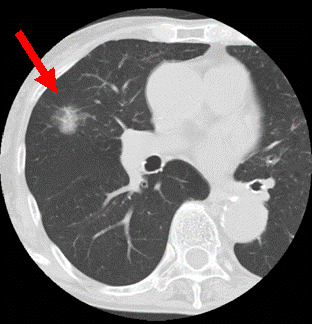

肺がんスクリーニング推奨の改訂 (USPSTF 2013)

肺がんのスクリーニング条件付きでB 推奨

The U.S. Preventive Services Task Force (USPSTF) recommends annual screening for lung cancer with low-dose computed tomography (LDCT) in persons at high risk for lung cancer based on age and smoking history.

推奨)ハイリスクグループに限り低線量CTによるスクリーニングを年1回推奨。

ハイリスクグループの定義

55歳から79歳の喫煙歴 1日1箱30年以上(30 pack-year or more)ブリンクマン指数では600以上。 かつ、禁煙後15年以上経過した人は除く

ここは日本の推奨と違うところ やるならLDCT! 単純+喀痰は検査としては不十分